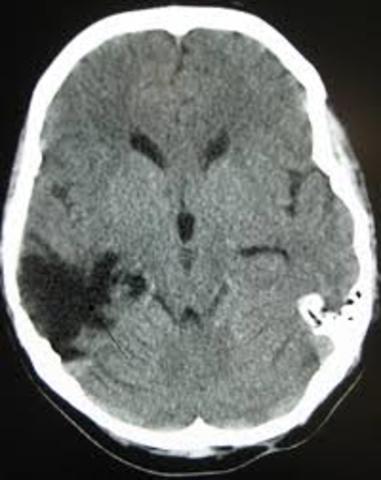

• Técnicas imagenològicas

La incorporación y difusión de las técnicas imagenològicas contemporáneas, en especial la escenografía cerebral o la tomografía axial computarizada TAC, implicó un verdadera revolución en todas las ciencias neurológicas.

Durante esta década se fortalece la investigación con el empleo de imágenes no ya anatómicas sino funcionales, en particular la resonancia magnética funcional y la tomografía por emisión de positrones, que han permitido visualizar la actividad cerebral durante la realización de diferentes tareas cognoscitivas.